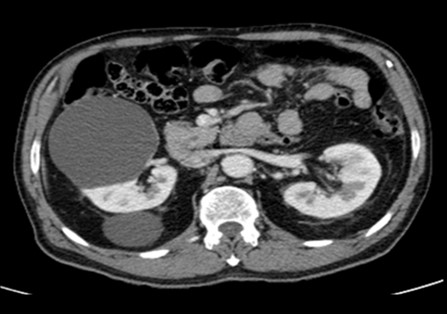

Clasificación Bosniak. Incidencia de hallazgos tomográficos en lesiones quísticas renales en pacientes entre mayo de 2022 y marzo de 2023

En los últimos años, la detección de tumoraciones renales ha aumentado debido al incremento en pruebas radiológicas. La tomografía computarizada (TC) ha resultado fundamental para diferenciar entre masas quísticas no quirúrgicas y quirúrgicas (…)